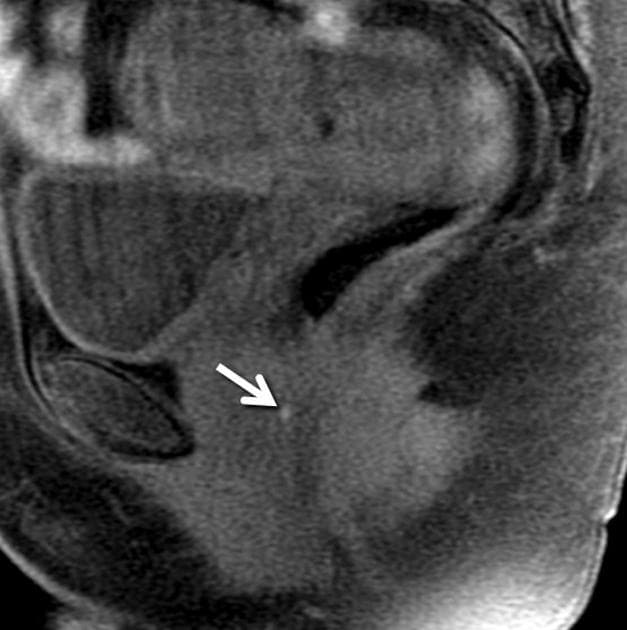

Tử cung, cả hai buồng trứng và trực tràng bị kéo sát lại gần nhau do các dải dính co thắt / xơ hóa, dẫn đến "dấu hiệu lá cỏ ba lá (cloverleaf sign)" – một hình ảnh mới được mô tả trong lạc nội mạc tử cung xâm lấn sâu (deep infiltrating endometriosis).

Hình ảnh minh họa dấu hiệu lá cỏ ba lá (cloverleaf sign) khi tử cung, cả hai buồng trứng và trực tràng bị kéo sát lại gần nhau do các dính co thắt, cho thấy lạc nội mạc tử cung xâm lấn sâu (deep infiltrating endometriosis).

- Dấu hiệu lá cỏ ba lá (cloverleaf sign) trong lạc nội mạc tử cung xâm lấn sâu gợi ý mạnh đến phẫu thuật phức tạp hơn, với thời gian mổ kéo dài hơn, nguy cơ phải cắt đoạn ruột cao hơn, và nguy cơ mất máu nhiều hơn.

- "Dấu hiệu lá cỏ ba lá trên cộng hưởng từ là hình ảnh đặc hiệu của lạc nội mạc tử cung xâm lấn sâu, đặc trưng bởi sự sát gần nhau của tử cung, hai buồng trứng và trực tràng do dính xơ hóa."

- "Các dải dính co thắt trong lạc nội mạc tử cung xâm lấn sâu có thể gây biến dạng giải phẫu nghiêm trọng và liên quan đến phẫu thuật phức tạp hơn, thời gian mổ kéo dài, và nguy cơ phải cắt đoạn ruột cao hơn."